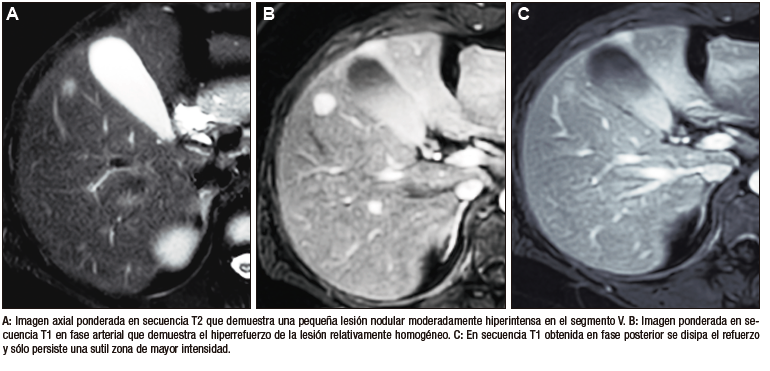

En la RM los hemangiomas son lesiones con señal

hipointensa en T1 e hiperintensa muy marcada en T2. Esta última característica los diferencia de otras

lesiones benignas o malignas, con excepción de los quistes, que presentan señal más elevada debido a su

contenido acuoso.1 El patrón de realce poscontraste es igual al que muestra la TC. (Figura 2) En

la secuencia de difusión no presentan un patrón restrictivo, si bien pueden exhibir una señal brillante en

valores b altos (parámetro que pondera la difusión); esto se debe al efecto brillo T2 y no a la restricción

verdadera, por lo que el mapa del coeficiente de difusión aparente (ADC, por sus siglas en inglés) muestra

señal y valores altos. En estudios con CHE son hipointensos en fase hepatobiliar ya que carecen de

hepatocitos. Una potencial causa de error puede ocurrir en algunos hemangiomas pequeños que presenten un

refuerzo precoz importante y que en fase de equilibrio (3 minutos) pueden presentarse hipointensos

(pseudolavado). De esta manera podrían ser malinterpretados como un CHC.2 No obstante, la

característica señal brillante de los hemangiomas en T2 es de utilidad para una tipificación

correcta.

Figura 2. Hemangioma en la RM. Imágenes axiales de la RM en secuencia T2 con

supresión grasa